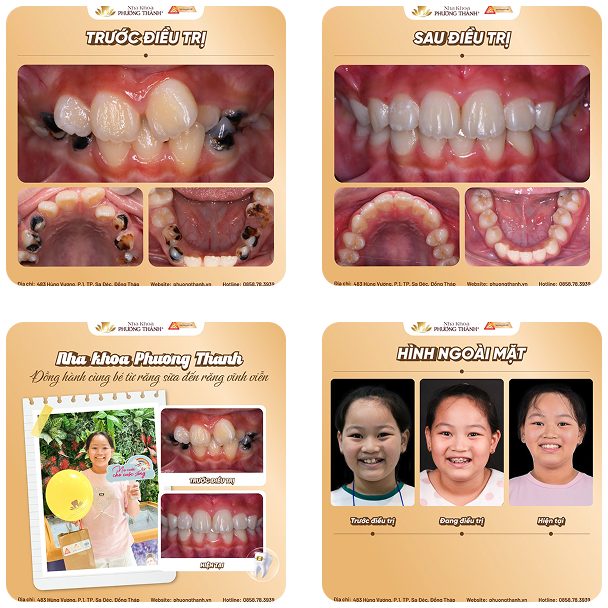

During this stage, parents should closely monitor their child’s tooth replacement process and schedule regular dental check-ups. This helps detect common abnormalities early, such as missing tooth buds, extra teeth in the midline gap, or impacted teeth (mesiodens), which can obstruct tooth eruption and affect the positioning of the remaining teeth.